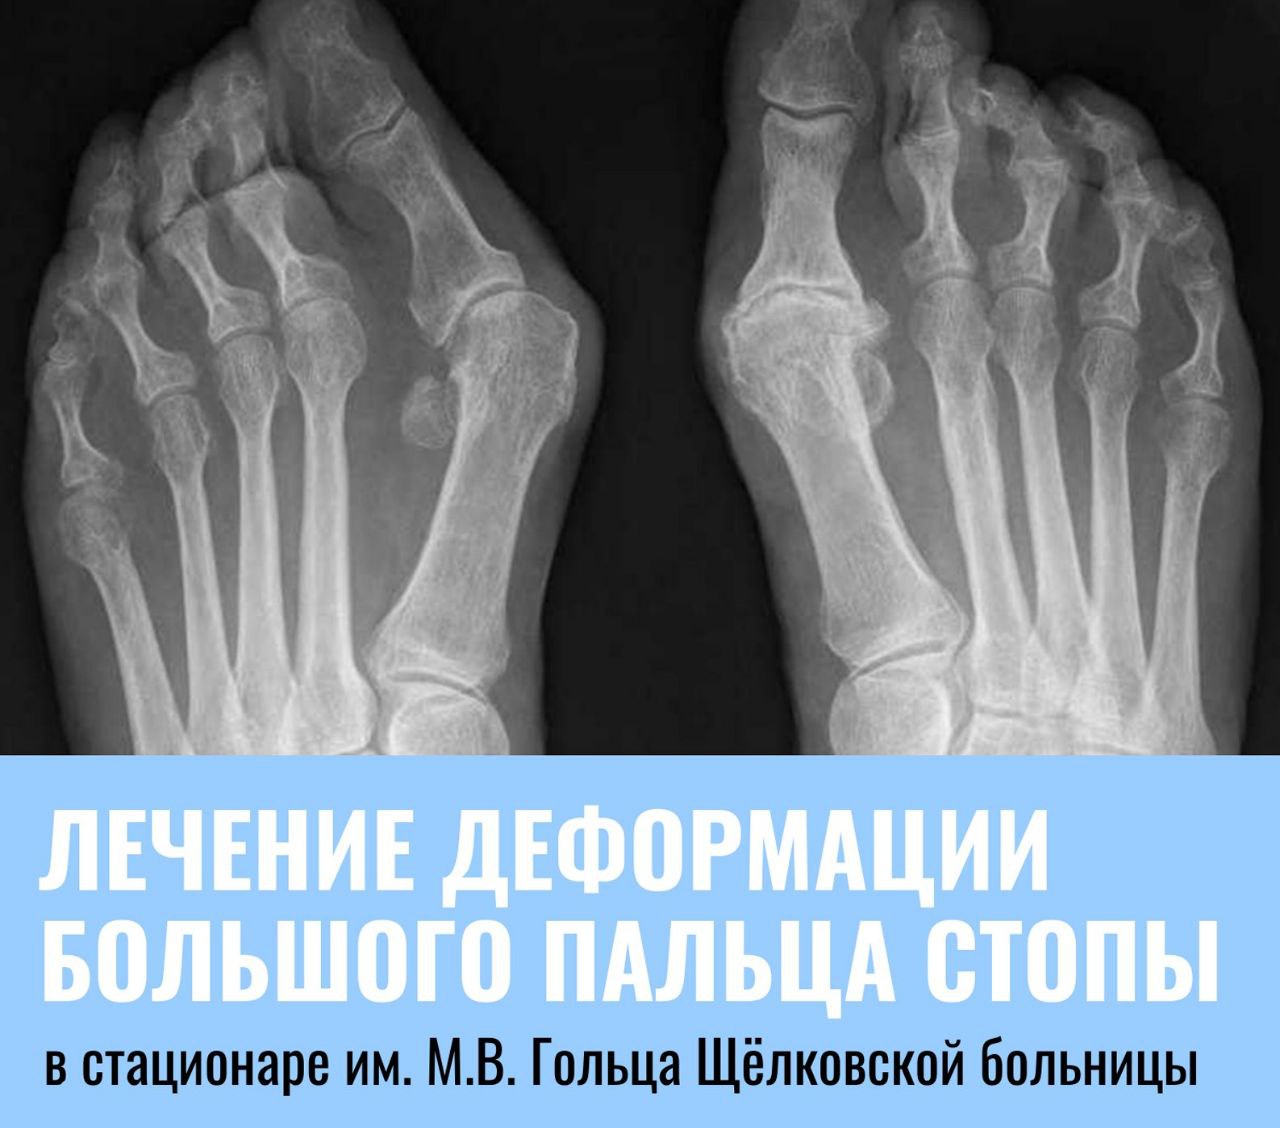

Лечение деформации большого пальца стопы в стационаре им. М.В. Гольца Щёлковской больницы

Вальгусная деформация большого пальца стопы (косточка на большом пальце) – это искривление, которое вызывает значительный дискомфорт и боль, особенно при ходьбе и ношении обуви. Лечение может быть консервативным (ортопедическая обувь, стельки, ЛФК, медикаменты) или хирургическим, в зависимости от степени деформации. 🩺 Жители Щёлково, Фрязино и Лосино-Петровского могут получить квалифицированную помощь в обособленном подразделении им. М.В. Гольца Щёлковской больницы во Фрязино. Здесь врачи-травматологи-ортопеды проведут консультацию, при необходимости направят на хирургическое лечение. В стационаре Щёлковской больницы операция по коррекции вальгусной деформации выполняется с применением современных высокотехнологичных методов. Преимущества этих вмешательств – малая травматичность и сниженный риск осложнений. 👉 Хирургическое лечение направлено на восстановление правильного положения большого пальца. 👉 Операция проводится под общим или спинальным наркозом и длится около полутора часов. 👉 Период стационарного лечения составляет от пяти до семи дней. 👉 Полное восстановление двигательных функций стопы, как правило, занимает около двух месяцев. Лечение проводится бесплатно по полису ОМС. 🤔 Консультации специалистов проходят каждую пятницу с 14:00 до 16:00 по адресу: г. Фрязино, ул. Московская, д. 7, корп. 5, каб. 313. Источник: Щёлковская больница |